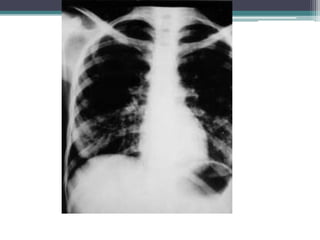

Radiografía de tórax con infiltrado

macronodular basal y medio, múltiple.

Caso Clínico Femenino de 12 años de edad con antecedente de atopia. Inició 15 días previos con mal estado general, hiporexia, astenia, adinamia e ictericia; se manejó como hepatitis en una clínica periférica. Cinco días después se agregó fiebre, tos en accesos y dificultad respiratoria progresiva con cianosis distal; se ingresó a terapia intensiva pediátrica con intubación nasotraqueal y ventilación mecánica. Radiografía de tórax con infiltrado macronodular basal y medio, múltiple.